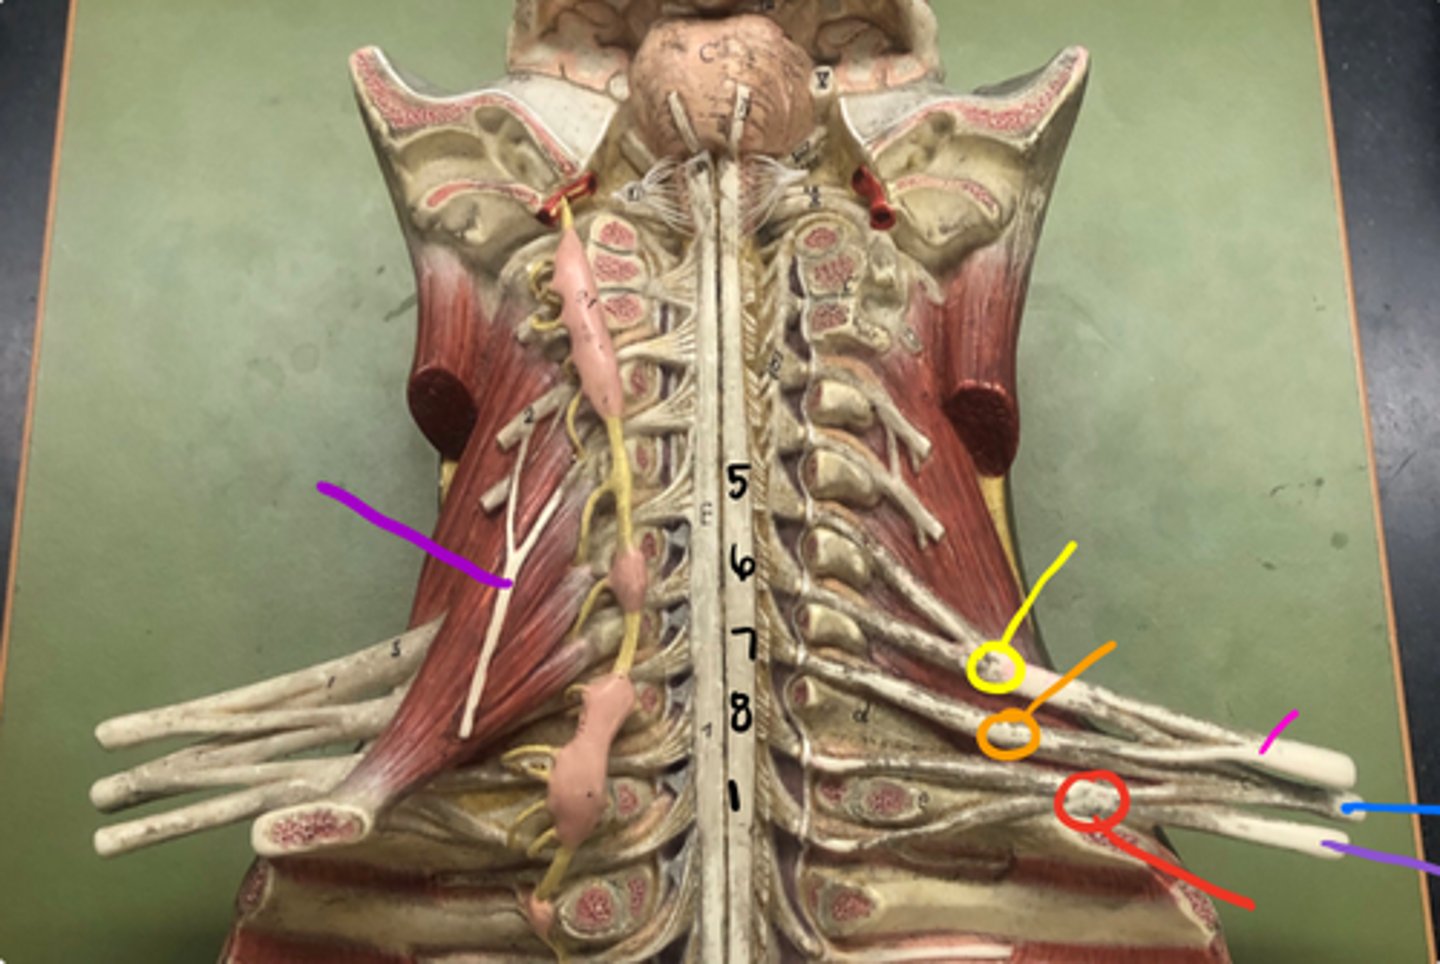

phrenic nerve

neon purple (on neck)

superior trunk

yellow

middle trunk

orange

inferior trunk

red

lateral cord

pink

medial cord

purple

posterior cord

blue